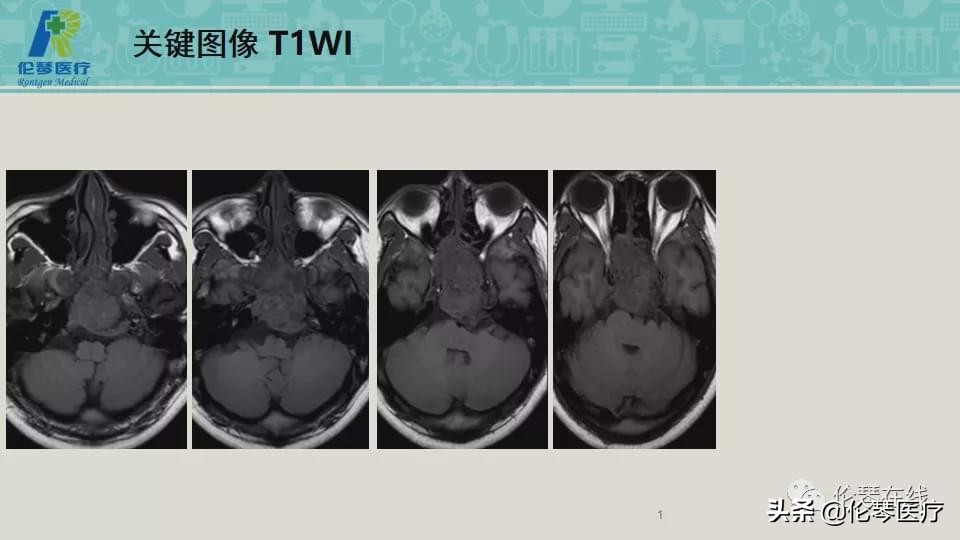

年龄:21岁

主诉:头痛,双眼内收、外展受限8个月,加重2月